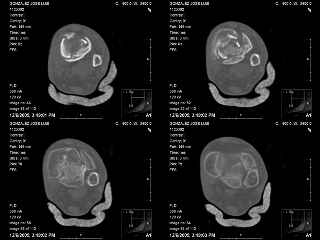

A 56 year old laborer fell off a wall approximately 5 months ago. He sustained an open pilon fracture. He was treated with debridement and external fixation. After he was treated for 4 months, the external fixator was removed.

The patient had no medical insurance and was therefore transferred to my care by his treating surgeon. He has remained NWB. He denies pain in his ankle. He has painless dorsiflexion and plantarflexion of his ankle joint.

I have attached his x-rays. I have also attached an WMV movie file of his axial CT (if you are unable to view this, I can post an MPEG file).